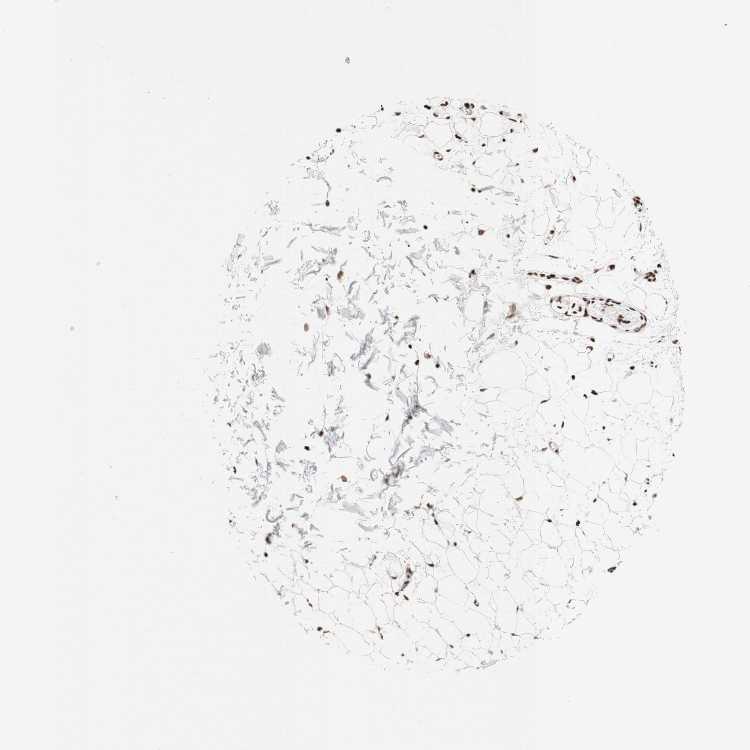

SOFT TISSUE 1 - Antibody stainingi

Antibody staining in the annotated cell types in the current human tissue is reported as not detected, low, medium, or high, based on conventional immunohistochemistry profiling in selected tissues. This score is based on the combination of the staining intensity and fraction of stained cells.

Each image is clickable and will lead to virtual microscopy that enables deeper exploration of all samples and also displays staining intensity scores, fraction scores and subcellular localization as well as patient and tissue information for each sample.

Antibody HPA036947Antibody HPA037363Antibody CAB012423

Chondrocytes --Medium

Fibroblasts LowNot detectedHigh

Peripheral nerve Not detectedMedium-